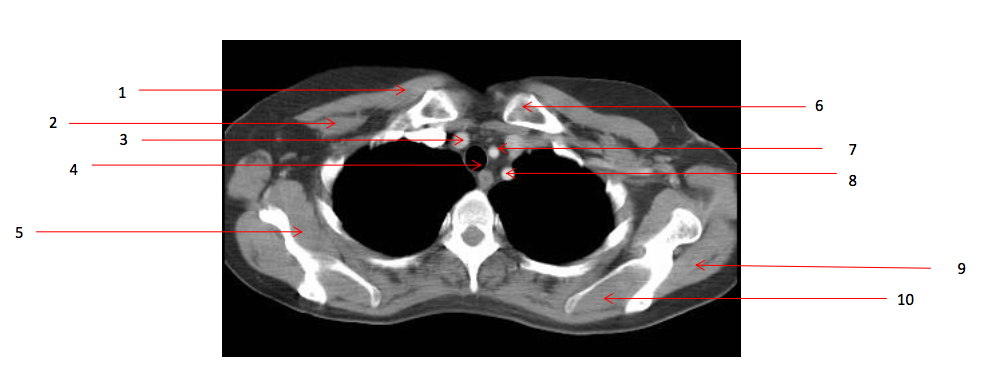

10

Number 13?

Rt erectae spinae muscle

11

Number 9?

Lt infraspinatus muscle

13

Number 16?

Lt scapula

14

Number 33?

15

Number 14?

Lt brachiocephalic vein

16

Number 17?

SVC

17

Number 11?

Sternum (manubrium)

20

Number 12?

Rt brachiocephalic vein

Number 15?

oesophagus